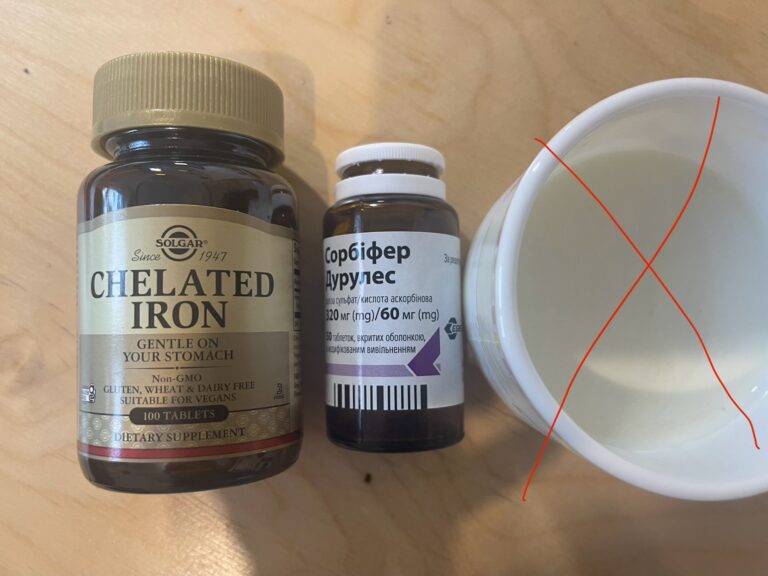

👩⚕️ Що таке гемоглобін і чому він такий важливий? Гемоглобін — це не просто...

Цей запит є доволі популярним. Адже все є ліки, і все є яд. Залежить...